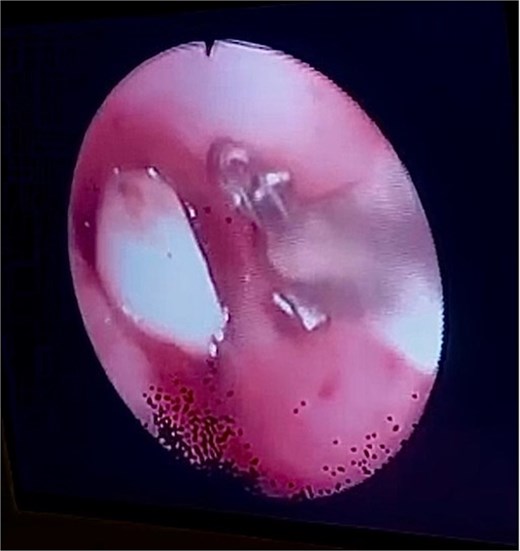

After obtaining informed and written consent, an emergency fiberoptic bronchoscopy was performed in the ICU on 20 October 2022. During the procedure, a FB was visualized at the origin of left mainstem bronchus. The decision was to extract the FB using endobronchial basket. However, the basket could not be deployed and opened in the left main bronchus due to the small size of the bronchus. To address this issue, the team utilized an endoscopic retrograde cholangiopancreatography (ERCP) balloon to mobilize the dental bridge from the left mainstem bronchus to the carina, facilitating the removal of the FB. Following that, the endobronchial basket was passed and opened to capture the dental bridge.

Bronchoscopy view showing the dental bridge lodged in the left mainstem bronchus.